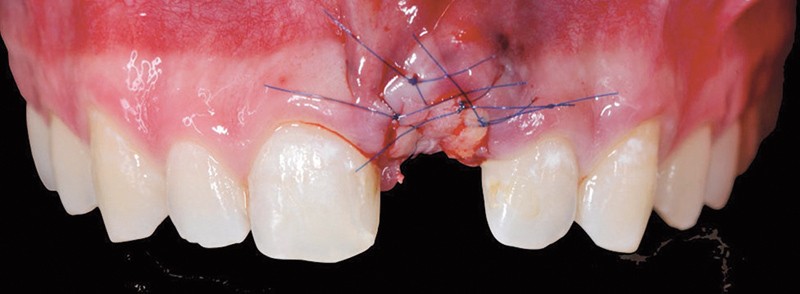

Nous sommes tous bien conscients de la problématique liée au remodelage osseux après extraction dentaire, en particulier dans la zone esthétique. Les conséquences cliniques sont telles que le recours à des techniques de régénération tissulaire est souvent nécessaire pour la pose de l’implant et pour assurer des résultats esthétiques. Cet article vise à démontrer l’efficacité d’un protocole d’optimisation tissulaire basé sur la préservation du capital osseux et sur l’optimisation des tissus gingivaux lors d’une extraction dentaire dans la zone esthétique. L’objectif de cet article est de suggérer un processus décisionnel en matière de technique chirurgicale, reposant d’une part, sur l’examen clinique initial et, d’autre part, sur une excellente compréhension du concept biologique.

L’aménagement des tissus durs et des tissus mous péri-implantaires dans la zone esthétique peut être géré dès l’extraction de la dent perdue, tout en privilégiant des procédures chirurgicales préventives comme les techniques de gestion d’alvéoles.